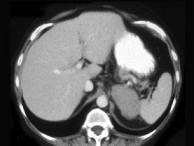

问题 女,47岁,满月脸、向心性肥胖伴高血压1个月,请结合所提供图像,作出诊断 ( )

选项 A、左肾上腺嗜铬细胞瘤 B、左肾上腺增生 C、左肾上腺腺癌 D、左肾上腺转移瘤 E、左肾上腺腺瘤

答案 C